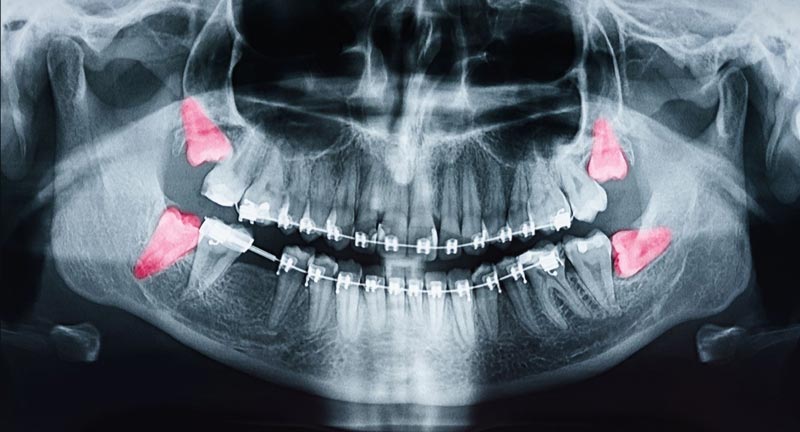

خیر، دندان عقل همیشه درنمیآید. در بسیاری از افراد، یک یا چند دندان عقل ممکن است بهطور کامل نهفته باقی بمانند و هرگز از لثه خارج نشوند. دلایل این اتفاق میتواند شامل کمبود فضای کافی در فک، موقعیت نادرست دندان یا موانع ساختاری در مسیر رویش آن باشد. در برخی افراد نیز تنها بخشی از دندان عقل رشد میکند و باقی آن زیر لثه باقی میماند که میتواند باعث مشکلاتی مانند التهاب و عفونت شود. بنابراین، رشد یا عدم رشد دندان عقل به ساختار فک، ژنتیک و عوامل دیگر بستگی دارد و برای بررسی دقیق آن، عکس برداری رادیولوژی لازم است.

کشیدن دندان عقل همیشه ضروری نیست و در برخی افراد، این دندان ها بدون مشکل رشد میکنند و نیازی به خارج کردن آنها وجود ندارد. اما زمانی که دندان عقل باعث بروز درد، التهاب، پوسیدگی دندان، فشار به دندان های کناری یا عفونت لثه شود، کشیدن آن توصیه میشود. همچنین اگر دندان عقل به صورت نهفته باقی بماند یا مسیر رشد نامناسبی داشته باشد که به ساختار فک آسیب بزند، باید توسط دندانپزشک متخصص بررسی و در صورت نیاز، خارج شود. دکتر آزادخواه، متخصص جراحی دهان و فک، توصیه میکند که ارزیابی وضعیت دندان عقل باید در سنین نوجوانی و جوانی انجام شود تا از عوارض احتمالی جلوگیری گردد.

علائم هشدار دهنده دندان عقل نهفته

دندان عقل نهفته زمانی رخ میدهد که فضای کافی برای رویش آن در دهان وجود نداشته باشد و در نتیجه، به طور کامل یا جزئی زیر لثه باقی بماند. این وضعیت میتواند بدون علامت باشد، اما در بسیاری از موارد، علائم هشداردهنده ای ظاهر میشود که نشان میدهد باید به دندانپزشک مراجعه کرد. علائم هشدار دهنده دندان عقل نهفته:

این علائم می توانند نشان دهنده عفونت، التهاب لثه یا حتی تشکیل کیست باشید و نیاز به بررسی تخصصی دارند.